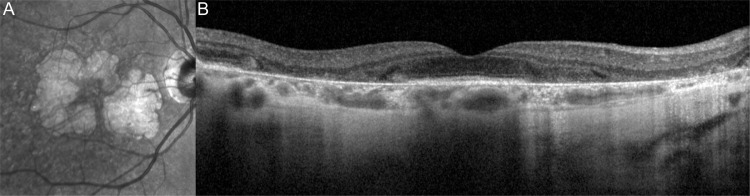

地理萎缩(GA)是一种晚期老年性黄斑变性(AMD),影响美国约100万人,全球约500万人。在这篇综述中,视网膜成像技术用于诊断和监测AMD中GA的进展,以及与GA发生和进展相关的危险因素。为了使临床医生熟悉GA患者的常见表型,强调了可能导致各种表型GA快速进展的临床和影像学特征。最近美国食品和药物管理局批准了新的GA治疗方法,可以减少病变的生长,了解GA进展的风险和导致GA生长的因素可能有助于患者选择和指导患者水平的管理和治疗。

Geographic atrophy (GA) is a form of advanced age-related macular degeneration (AMD) affecting approximately 1 million people in the USA and 5 million globally. In this review, retinal imaging techniques used for diagnosis and monitoring progression of GA in AMD, and the risk factors associated with the development and progression of GA are summarised. To familiarise clinicians with common phenotypes of patients with GA, the clinical and imaging features that may lead to rapid progression of GA in various phenotypes are highlighted. With the recent US Food and Drug Administration approval of new GA treatments that reduce lesion growth, understanding the risk of progression to GA and factors contributing to GA growth may aid in patient selection and guide patient-level management and treatment.